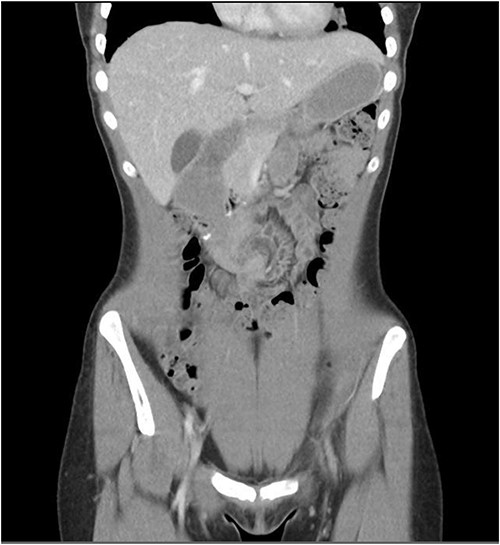

She presented to the surgeon’s rooms with a history of 9 days of postprandial vomiting 9 months later. A computed tomography (CT) showed a volvulus immediately adjacent to the duodenojejunostomy anastomosis causing a small bowel obstruction (Fig. 2).

The patient was taken for a diagnostic laparoscopy and found to have an internal hernia. Small bowel had fallen through a defect between the afferent limb of the jejunum and the third part of the duodenum (Fig. 3). This was reduced, the small bowel was run and found to be viable with no need for resection. The defect was closed with 3.0 V-lock suture.